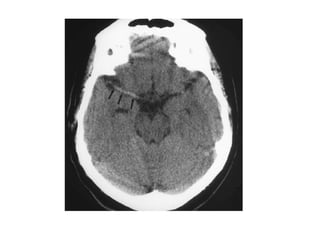

1-Normal :

-Initial appearances often normal in first few